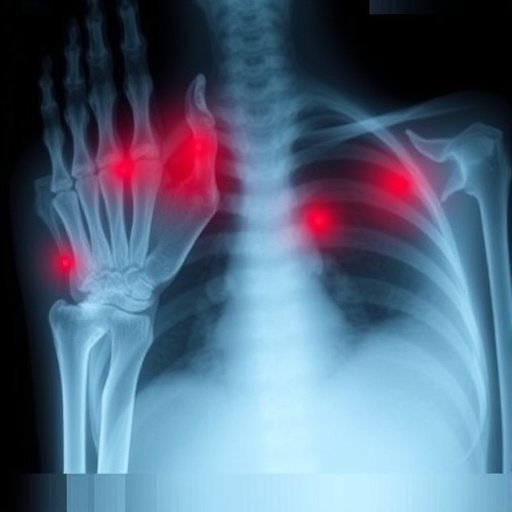

Li-Fraumeni Syndrome remains a daunting challenge in oncogenetics due to its rarity and the heterogeneity of cancer manifestations it engenders, which include sarcomas, breast carcinomas, brain tumors, and leukemias among others. Historically, detection protocols have hinged upon the Chompret criteria, a set of binary clinical benchmarks endorsed by the National Comprehensive Cancer Network (NCCN), designed to determine candidacy for TP53 genetic testing. However, these criteria often falter when faced with atypical or incomplete family histories, resulting in missed diagnoses and unwarranted psychosocial distress stemming from negative tests in low-risk individuals.